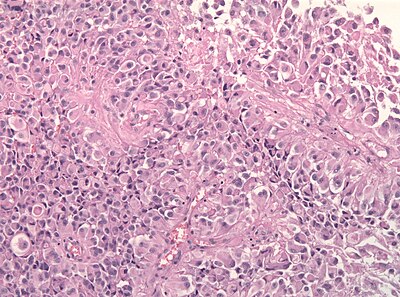

1

Diagnosis?

Epitheloid glioblastoma HE.jpg

Pilocytic astrocytoma

Diffuse Astrocytoma

Pleomorphic xanthoastrocytoma

Subependymal giant cell astrocytoma

Oligodendroglioma

Glioblastoma, classic

Glioblastoma, epitheloid

Giant cell glioblastoma

Gliosarcoma

Ependymoma

Subependymoma

Myxopapillary ependymoma

Ganglioglioma

Choroid plexus papilloma

Angiocentric glioma

Dysembryoplastic neuroepithelial tumour

Neurocytoma

Paraganglioma

Pineocytoma

Papillary glioneuronal tumour

Medulloblastoma

CNS PNET